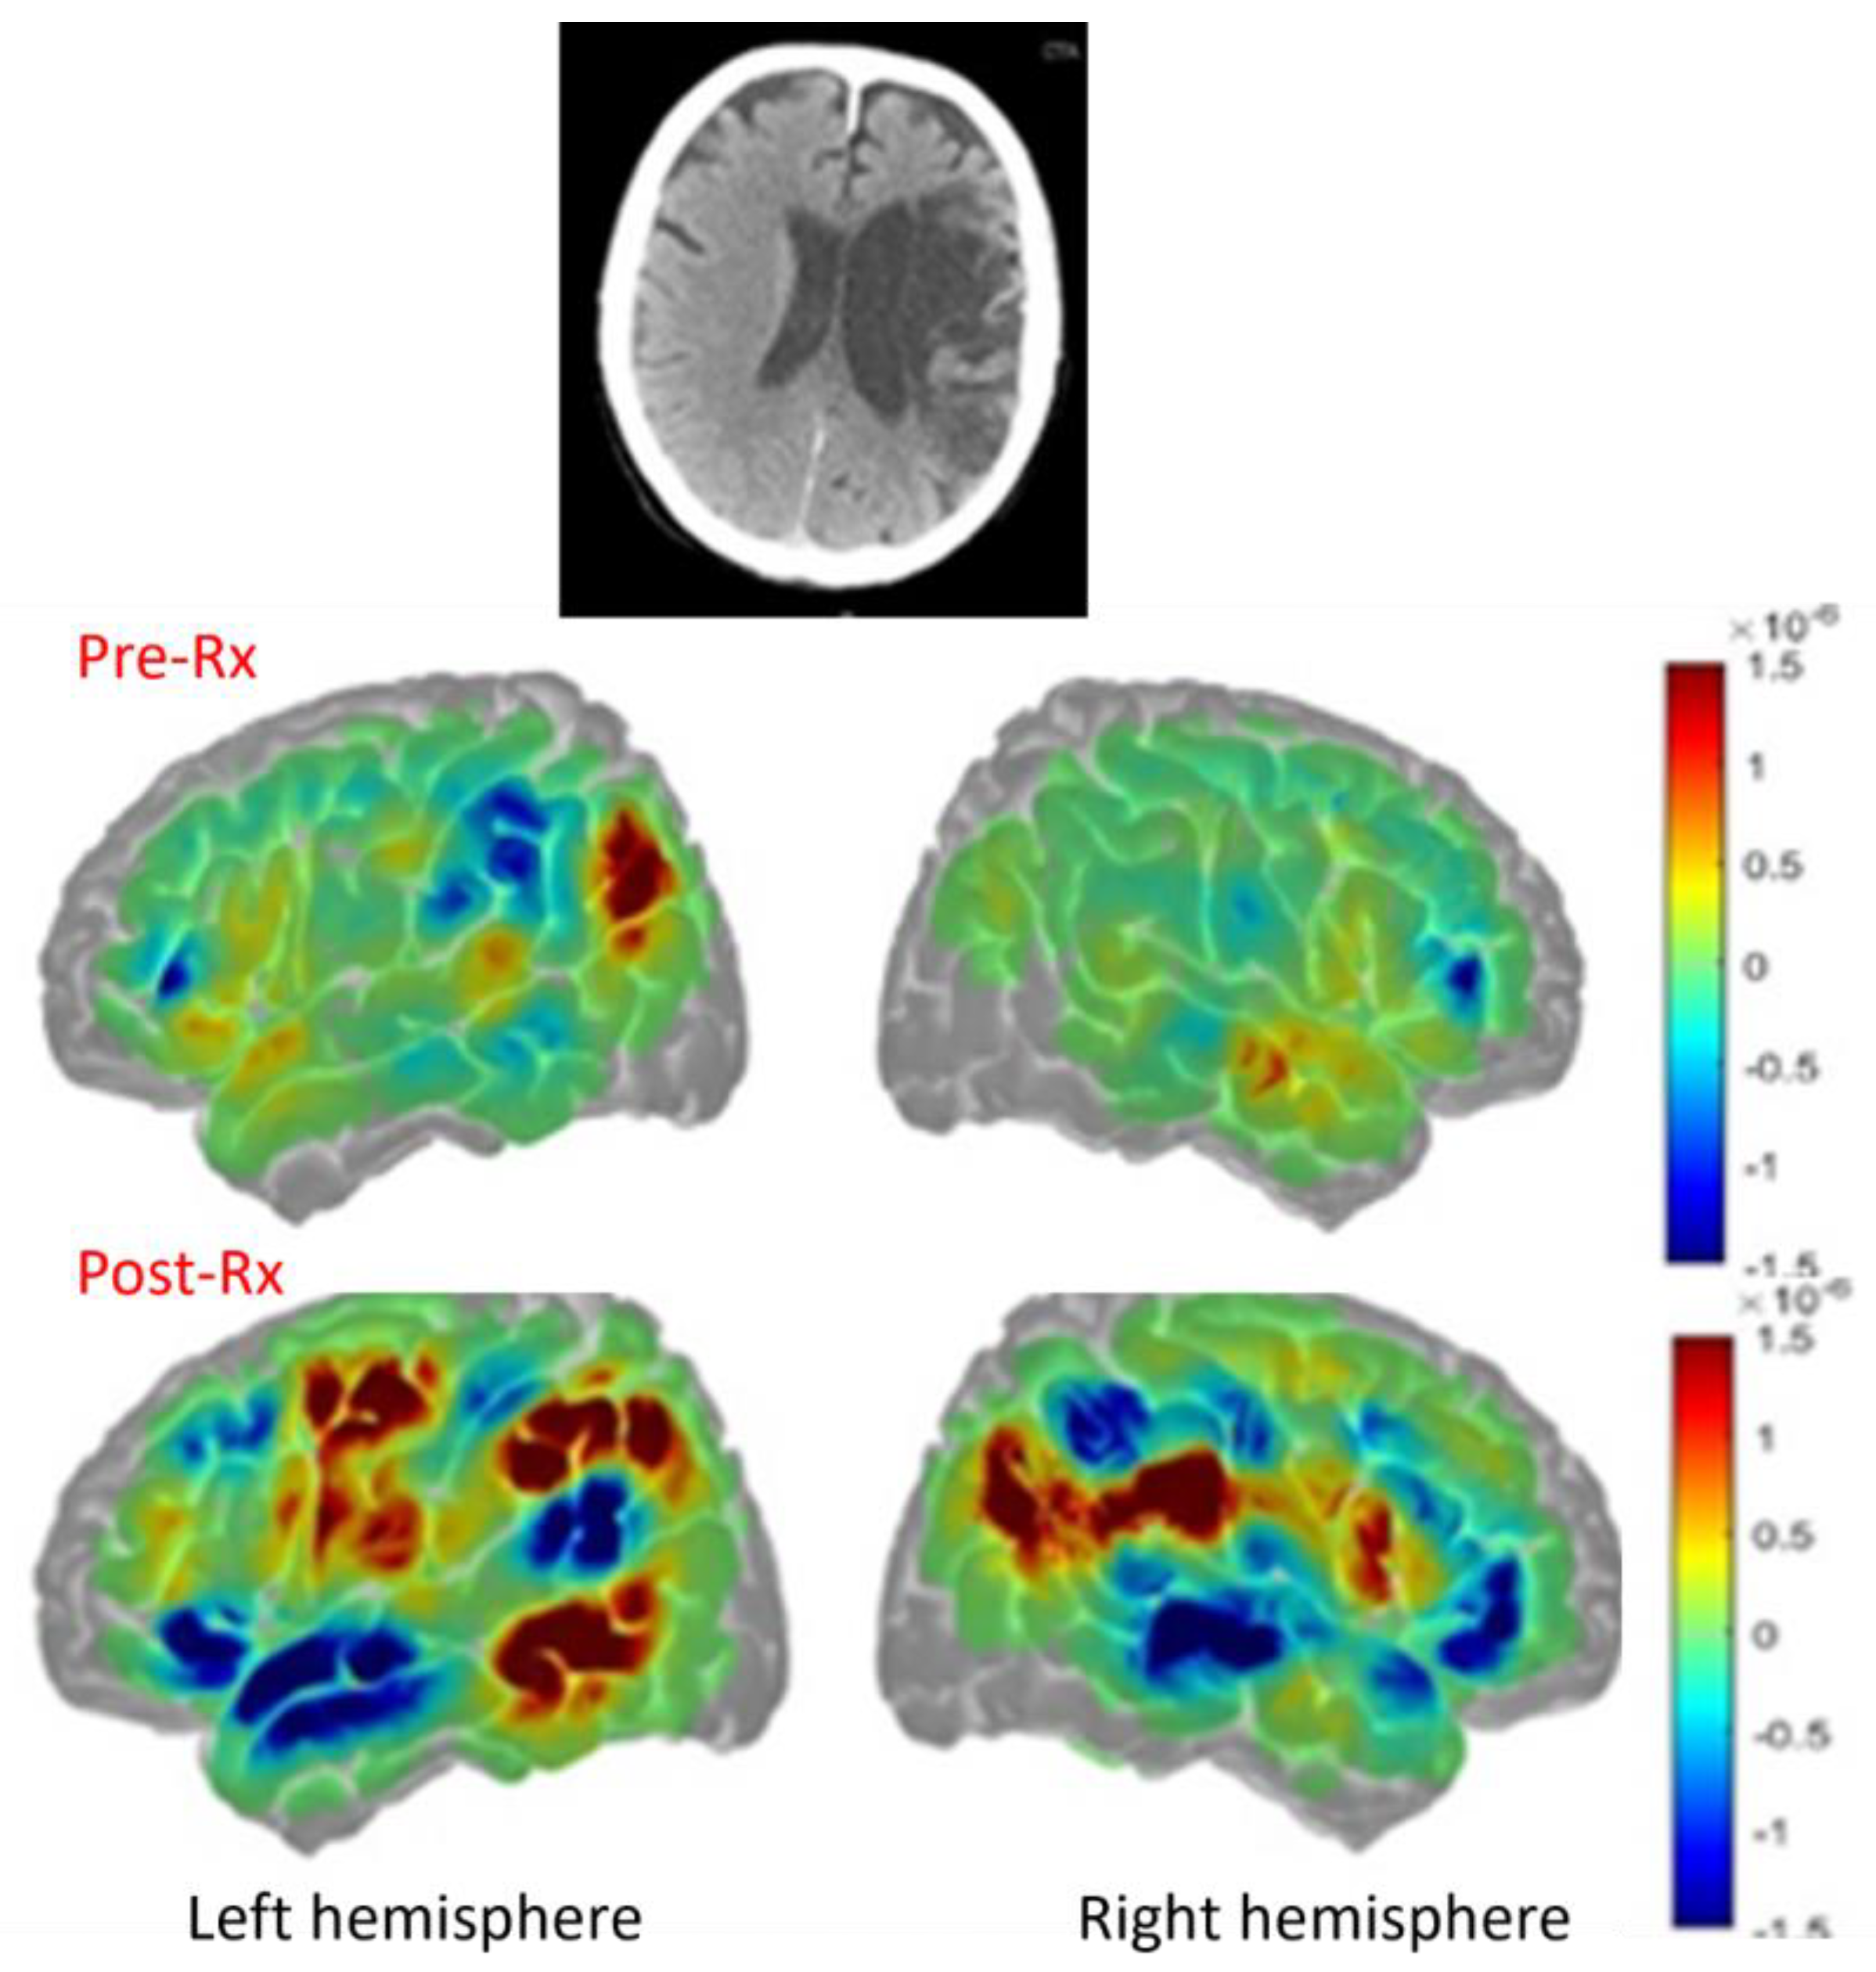

In contrast, a participant in the same randomized trial who had a large left MCA stroke with damage to the left hemisphere language cortex showed poor subacute recovery, but did produce more intelligible words after treatment. This individual with global aphasia two months post-stroke involving language network (Figure 8, top panel) showed increased perilesional left language cortex activation (especially in left temporal and parietal cortex, Figure 8 (left lower panel) but also increased activation in some right hemisphere homologues (right lower panel) compared to pre-treatment (middle panerl) and also compared to controls, as shown in Figure 7, top panel) with increased intelligible word production [35].

Figure 7. Top panel. Large left middle cerebral artery infarct. Middle panel. Pre-treatment activation in red [HbO]. Lower panel. Post-treatment activation with naming in red, with substantial increases in left frontal, parietal, and temporal cortex and right frontal and parietal cortex.